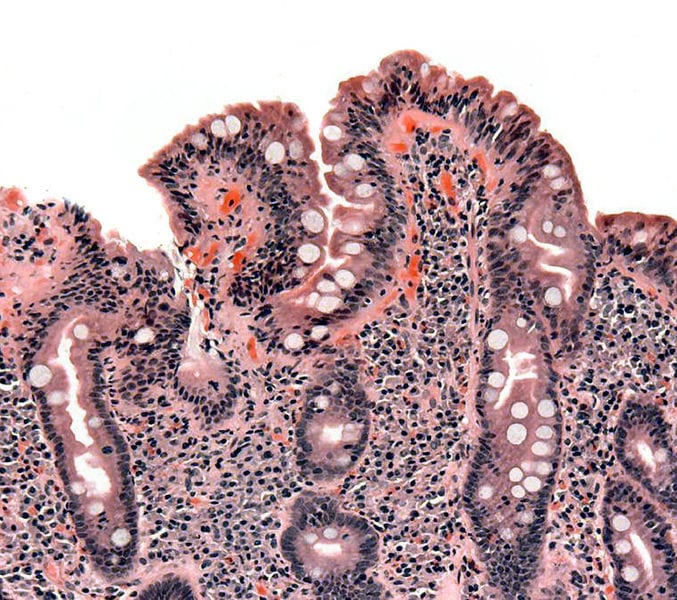

Blunting of villi commonly seen in villous atrophy (causing malabsorption). Courtesy of Samir at Wikipedia.

Benicar is prescribed to treat hypertension and contains the active ingredient olmesartan. One side effect of Benicar is villous atrophy. Villous atrophy is a condition which causes some users to be hospitalized for weeks or months as a result of being unable to properly absorb food and water. Furthermore, as a result of not properly absorbing nutrients into the body for months or years, Benicar users can become severely dehydrated and malnourished and often are hospitalized for long periods of time as a result of kidney failure, or hypokalemia. They require IV fluids and nourishment to be fed to them directly into their bloodstream. Unfortunately for the users of Benicar, neither they nor their physicians had any idea of the devastating side effects caused by Benicar.